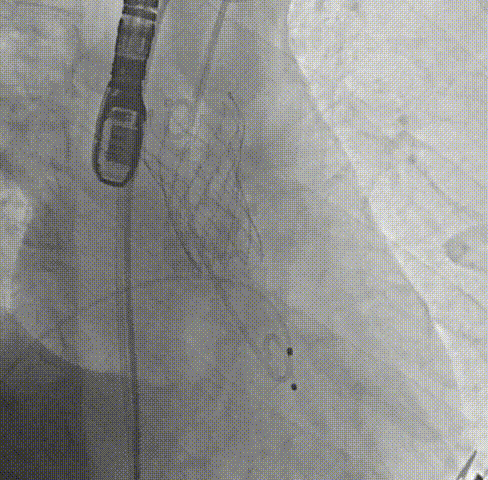

周达新教授 复旦大学附属中山医院 共识引路,干瓣启新,共赴临床解决方案:当前,结构性心脏病的介入治疗已迈入微创化、精准化的新时代。技术的革新、创新器械的上市,都是我们中国技术领跑的印证,《专家共识》的应运而生是中国医生对于行业“规范化”的践行,让治疗更精准、让医者更贴近“以患者为中心”的医疗本质。 潘文志教授 复旦大学附属中山医院 严谨求真重思考 创新临床互验证:在医学的漫长征途中,新器械的突破与严谨的临床研究是两大核心驱动力。拥抱创新的同时需要严谨求证,预装干瓣作为创新器械,其即取即用的特性可以很好的适配“急诊”的场景,此外,国产创新不是简单的复制,干瓣的瓣叶质地不是字面意思“干”的,而具“曲柔性”。所以,需要多看多测,才能全面了解一款产品。《经导管心脏瓣膜治疗术》的问世也是凝结着我们带着临床思维思考的结晶的“独家秘笈”,希望能够将“来时的路”变成未来行业同行者的“高效学习之路”! 患者病史 多病共存陷困境,主动脉瓣狭窄成 “首要威胁” 现病史:患者反复活动后胸闷2年余,无胸痛、心悸,无头晕、晕厥等不适,未予重视。患者轻微体力活动(快走、爬楼梯)即胸闷气促,静息及夜间无不适,无咳嗽、心悸等症状。为进一步诊疗收入我科,患病以来精神、食欲、睡眠、二便及体重均正常。 既往史: 2025年5月7日因小便不畅至外院住院病理穿刺确诊前列腺癌,期间检查心超提示主动脉瓣钙化伴重度狭窄,遂暂缓前列腺手术。2025年05月30日至我院就诊。 2025年5月20日开始服用比卡鲁胺片。患者血脂异常,长期服用丹参滴丸,麝香保心丸,心通颗拉。 手术史外伤史:10年前行肺手术,具体不详。否认外伤史。 入院检查 心电图提示:窦性心动过缓;ST-T改变; 心超显示:主动脉瓣钙化伴重度狭窄及轻度反流,Vmax 4.8m/s、PGmax 93mmHg、PGmean 47mmHg;左房增大,左室壁增厚。 冠状动脉CT造影:左前降支中段浅表心肌桥,主动脉瓣增厚伴重度钙化,主动脉粥样硬化。 术前CT 三叶瓣,中度钙化,主动脉根部直径25.4mm,LVOT直径23.5mm 双侧冠脉开口高度尚可,瓦氏窦尚可,ST尚可,升主尚可,冠脉风险小;中度钙化,心脏角度39.2°;心腔内径可,左室壁增厚。 外周走行尚可,全主动脉存在散在钙化,右侧穿刺点需避开钙化,血管内径可,血管内壁存在纤维增厚。 手术策略:右侧股动脉为主入路,使用20F大鞘;20球囊预扩,植入AV29瓣膜; 手术过程 主动脉根部造影 输送系统柔顺过弓 定位 缓慢释放瓣膜 造影观察 稳定脱钩 最终造影性钙位置良好,轻微瓣周漏 术后超声:轻度瓣周漏,术后平均压差11mmHg 出院前超声:平均压差11mmHg 在多基础疾病患者日益增多的当下,该病例也为临床提供重要启示:针对合并肿瘤、既往手术史的复杂瓣膜病患者,需通过多学科协作(心内科、肿瘤科、麻醉科等)全面评估病情,结合精准影像技术与适配器械,制定个体化手术方案,才能在保障安全的同时,实现最优疗效。 作为中国结构性心脏病领域的标杆学术活动,中国结构周 2025为这类高水平临床病例提供了交流平台,助力推动我国结构性心脏病诊疗技术持续创新,让更多复杂瓣膜病患者受益于精准医疗方案。 ProStyle A®预装干瓣——助力临床最优化解决方案: 轻松过弓,精准可控:该病例全主动脉存在散在钙化,右侧穿刺点需避开钙化,ProStyle A®较细的尺寸+柔顺的输送系统通过性能得到了很好的验证; 平稳释放:平衡的径向支撑力降低了释放过程中的张力,流入端小锥角设计能够迅速锚定贴边; 预装干瓣 便捷顺安:金仕生物专利抗钙化技术运用纳米技术去除组织内的细胞碎片和磷脂,封闭游离醛基,从根本上阻断了瓣膜钙化的多项因素,显著提升了瓣膜的耐久性;同时,相比较传统戊二醛保存方式,干式存储最大限度的保留心包的亲水亲油平衡,还原组织天然曲柔性,进一步保障了瓣叶开合,保证长期耐久性; 专家简介 葛均波 复旦大学附属中山医院(点击查看专家详细简历) 周达新 复旦大学附属中山医院(点击查看专家详细简历) 潘文志 复旦大学附属中山医院(点击查看专家详细简历) · END ·